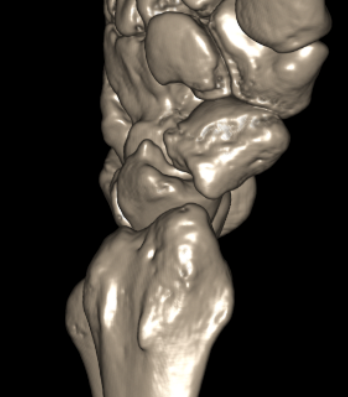

CT

Indication

- diagnose nonuion

- identify humpback deformity

- plan size and shape of bone graft

Failure of fracture to unite at 3 months on CT scan

Nonunion with flexion deformity